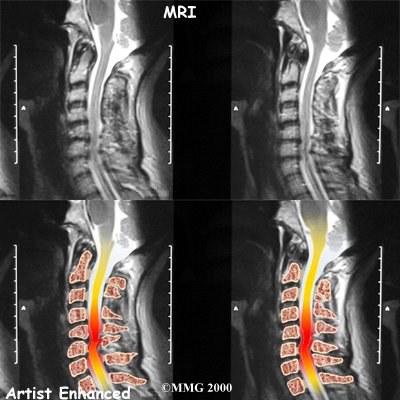

The magnetic resonance imaging (MRI) scan uses magnetic waves to create pictures of the cervical spine in slices. The MRI scan shows the cervical spine bones, as well as the soft tissue structures such as the discs, joints, and nerves.

MRI scans are painless and don't require needles or dye. The MRI scan has become the most common test to look at the cervical spine after X-rays have been taken.

Stenosis means closed in. Spinal stenosis refers to a condition in which the spinal cord is closed in, or compressed, inside the tube of the spinal canal. Spinal stenosis may be caused by degenerative changes, such as bone spurs pushing against the spinal cord within the spinal canal.

Spinal Stenosis

However, stenosis can also develop when a person of any age has a disc herniation that pushes against the spinal canal. When the spinal cord is squeezed in the neck, doctors call the condition cervical myelopathy. This is an alarming condition that demands medical attention. Cervical myelopathy can cause problems with the bowels and bladder, change the way you walk, and affect your ability to use your fingers and hand.

Cervical Myelopathy